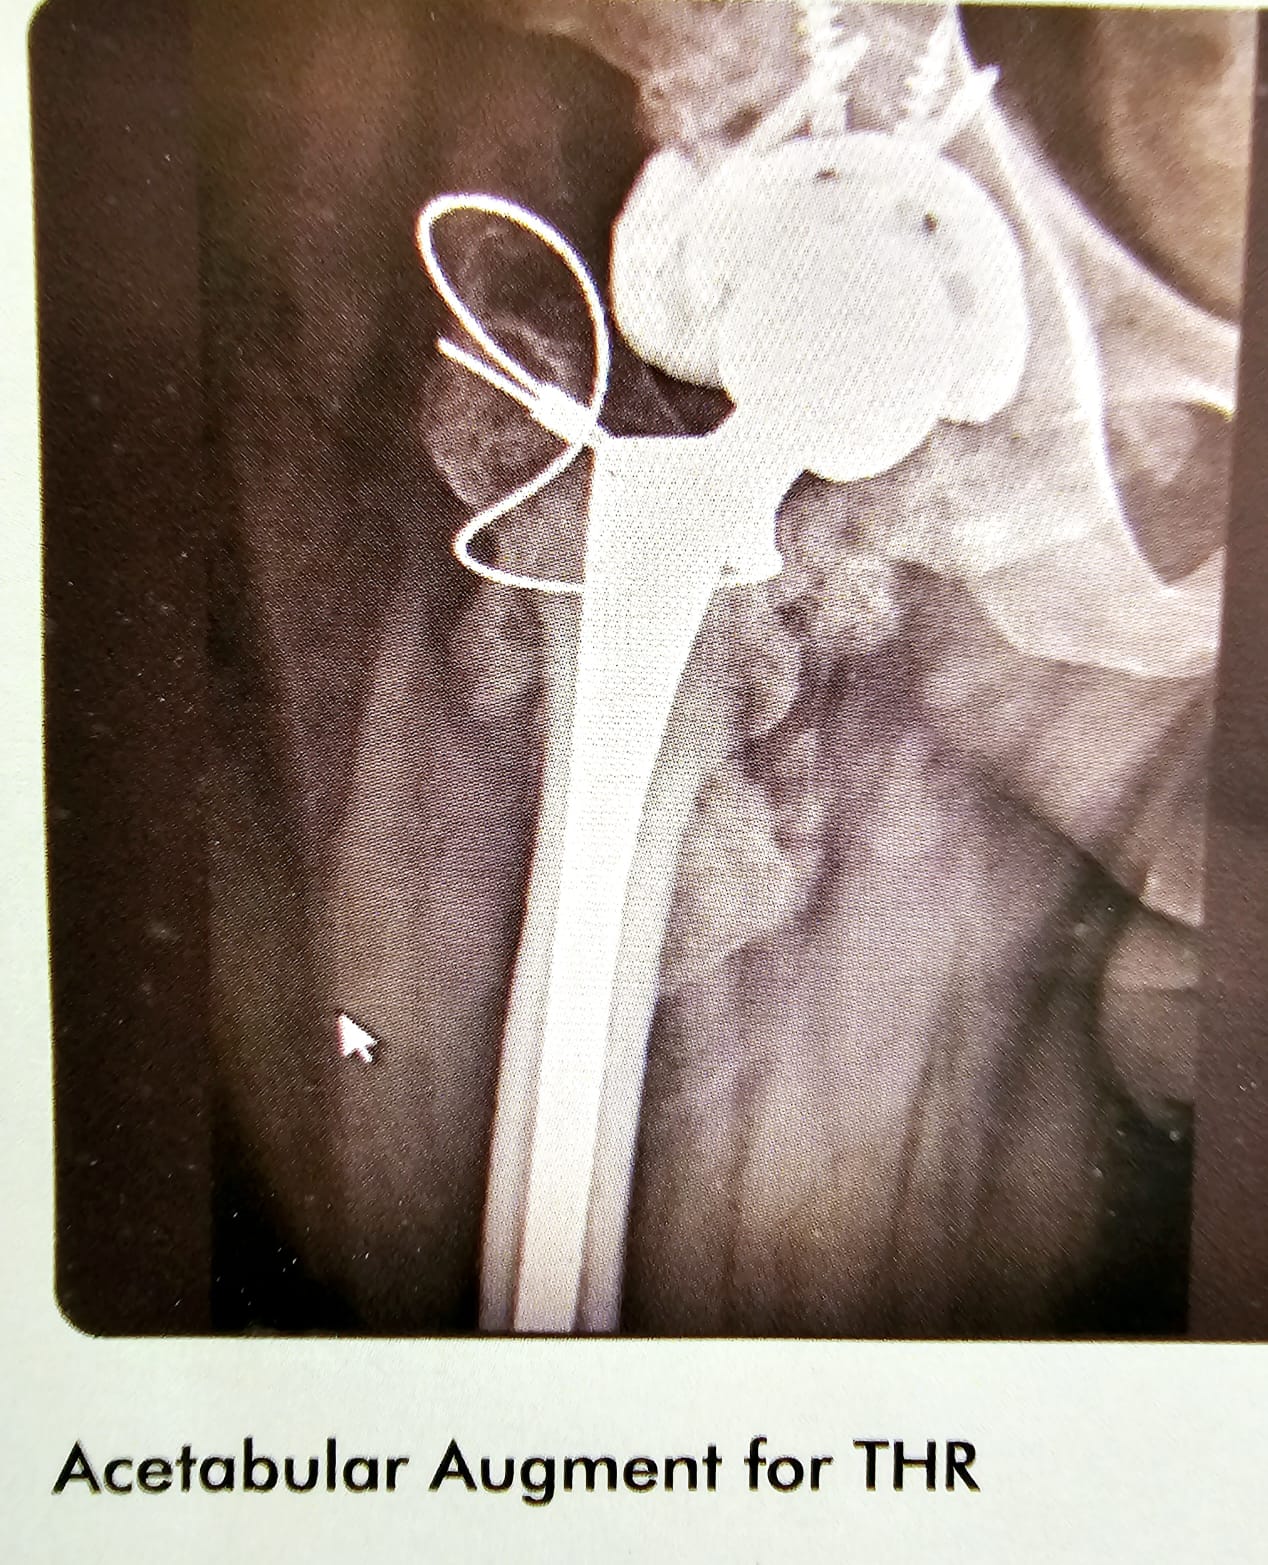

Acetabular Augment for THR

This lady has the revision of the Right THR with acetabular augment and circulage wiring of the GT. It was a case THR which has failed twice, but this time with the help of acetabular augment and wiring of the trochanters, she did extremely well. This is shown for the complexity of the case